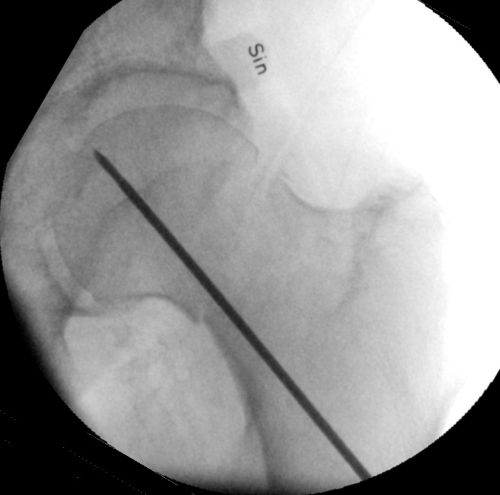

- Borra med k-tråd, tråden ska gå nära kollums distala kortex i frontalbild och centralt i kollum i sidobild. Änden på k-tråden ska sluta ca 5 mm från kaputs broskkant.

- Låt k-tråden sitta kvar, borra över den med kanylerat borr, använd hylsa. Borra tills änden är ca 0,5 cm från broskkanten. Läs av längd på borret mot hylsans kant, avrunda uppåt och välj denna längd på spik.